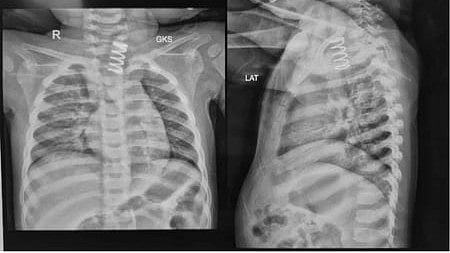

"An X-ray examination revealed a shocking finding -- a large metallic spring was lodged in the upper part of the oesophagus," Dr Jain said.

Initial endoscopic attempts at removal at a private hospital revealed that the object was severely impacted, with significant ulceration and swelling of the surrounding oesophagal lining, he said.

Given the high risk of perforation, the metallic spring's removal was deemed unsafe and the child was referred urgently to AIIMS for advanced care.